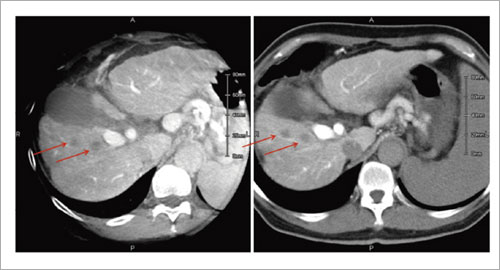

MPR像に関しては,厚みを加算することで画質を上げることは可能であるが,Low Contrast Imagingではおよそ1〜3mm程度の厚みで十分な画像が得られている(図5)。そのためMPR像だけではなく,ボリュームレンダリングとしてもこれまでの3D-Angioと同じように高画質を実現できている(図6)。

図5 CTAP

a:Low Contrast Imaging(3mm厚)

b:シングルスライスCT(7mm厚)

→は大きさ6mm程度の肝細胞がん |